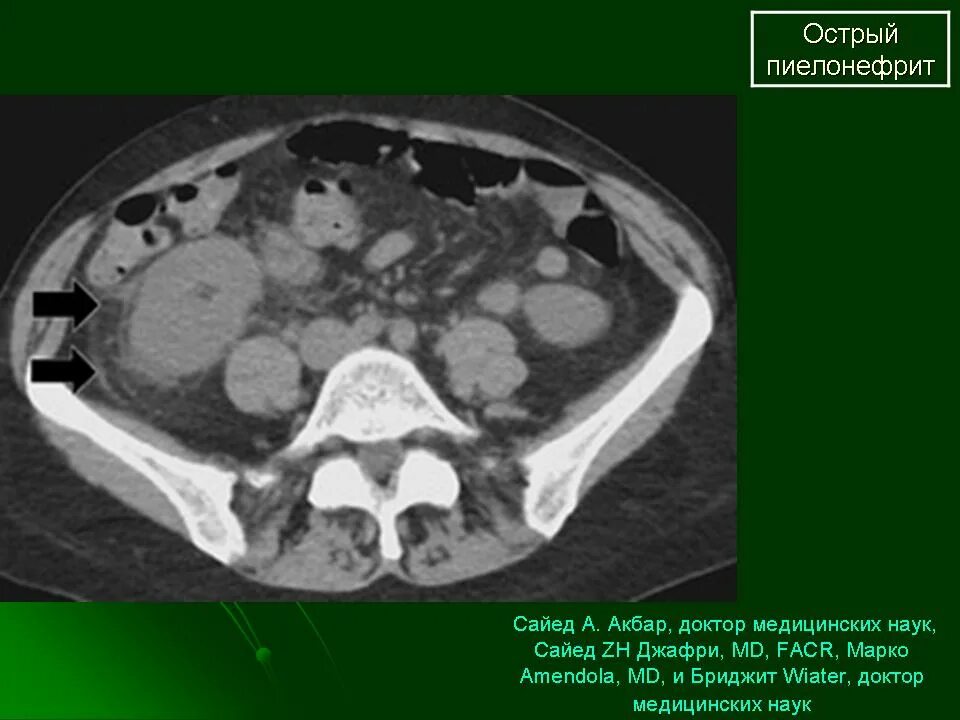

Пиелонефрит кт